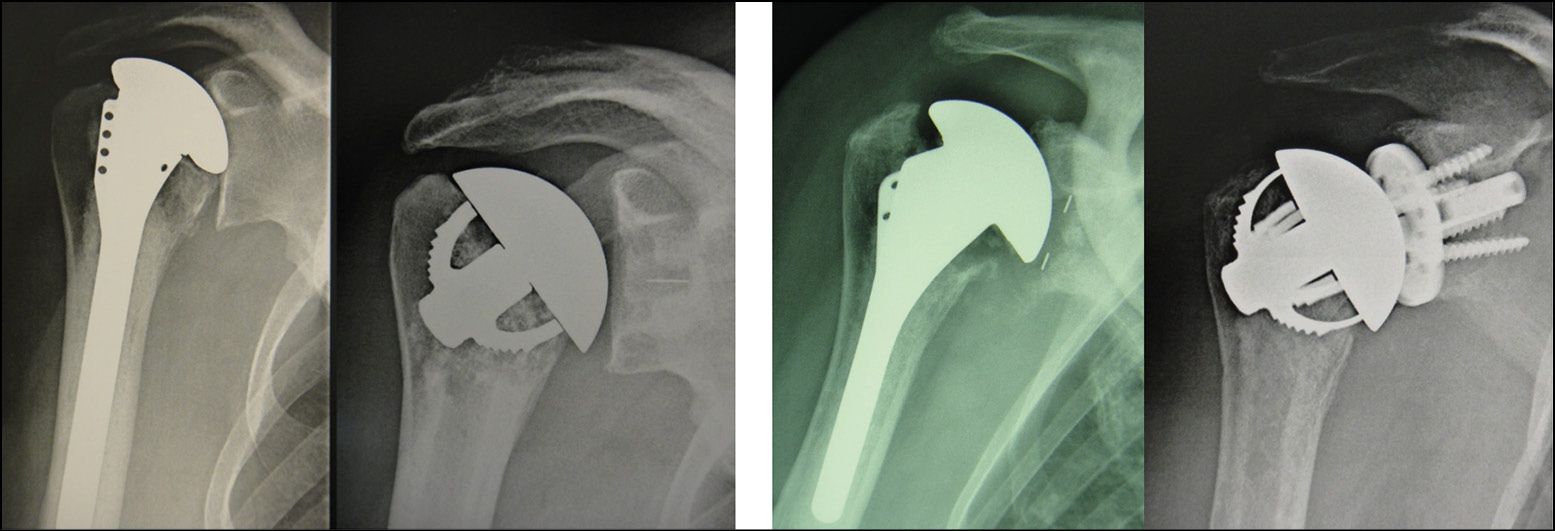

Minimally-invasive conversion of TSAa to TSAr in case of cuff failure following stemless anatomical arthroplasty: if a conversion to reverse is required, it can sometimes be possible to keep the stemless implant, especially if either or both of the humeral and glenoid components are universal. If the humeral component is not convertible, its mandatory removal does not preclude the use of another stemless implant, provided the epiphyseal bone has not been overly weakened (Fig. 17).

De-escalation during revision of a poorly-positioned humeral stem in a young subject is another option offering elegant simplicity. The cement sheath can even be left in place provided there is no sepsis (Fig. 18).